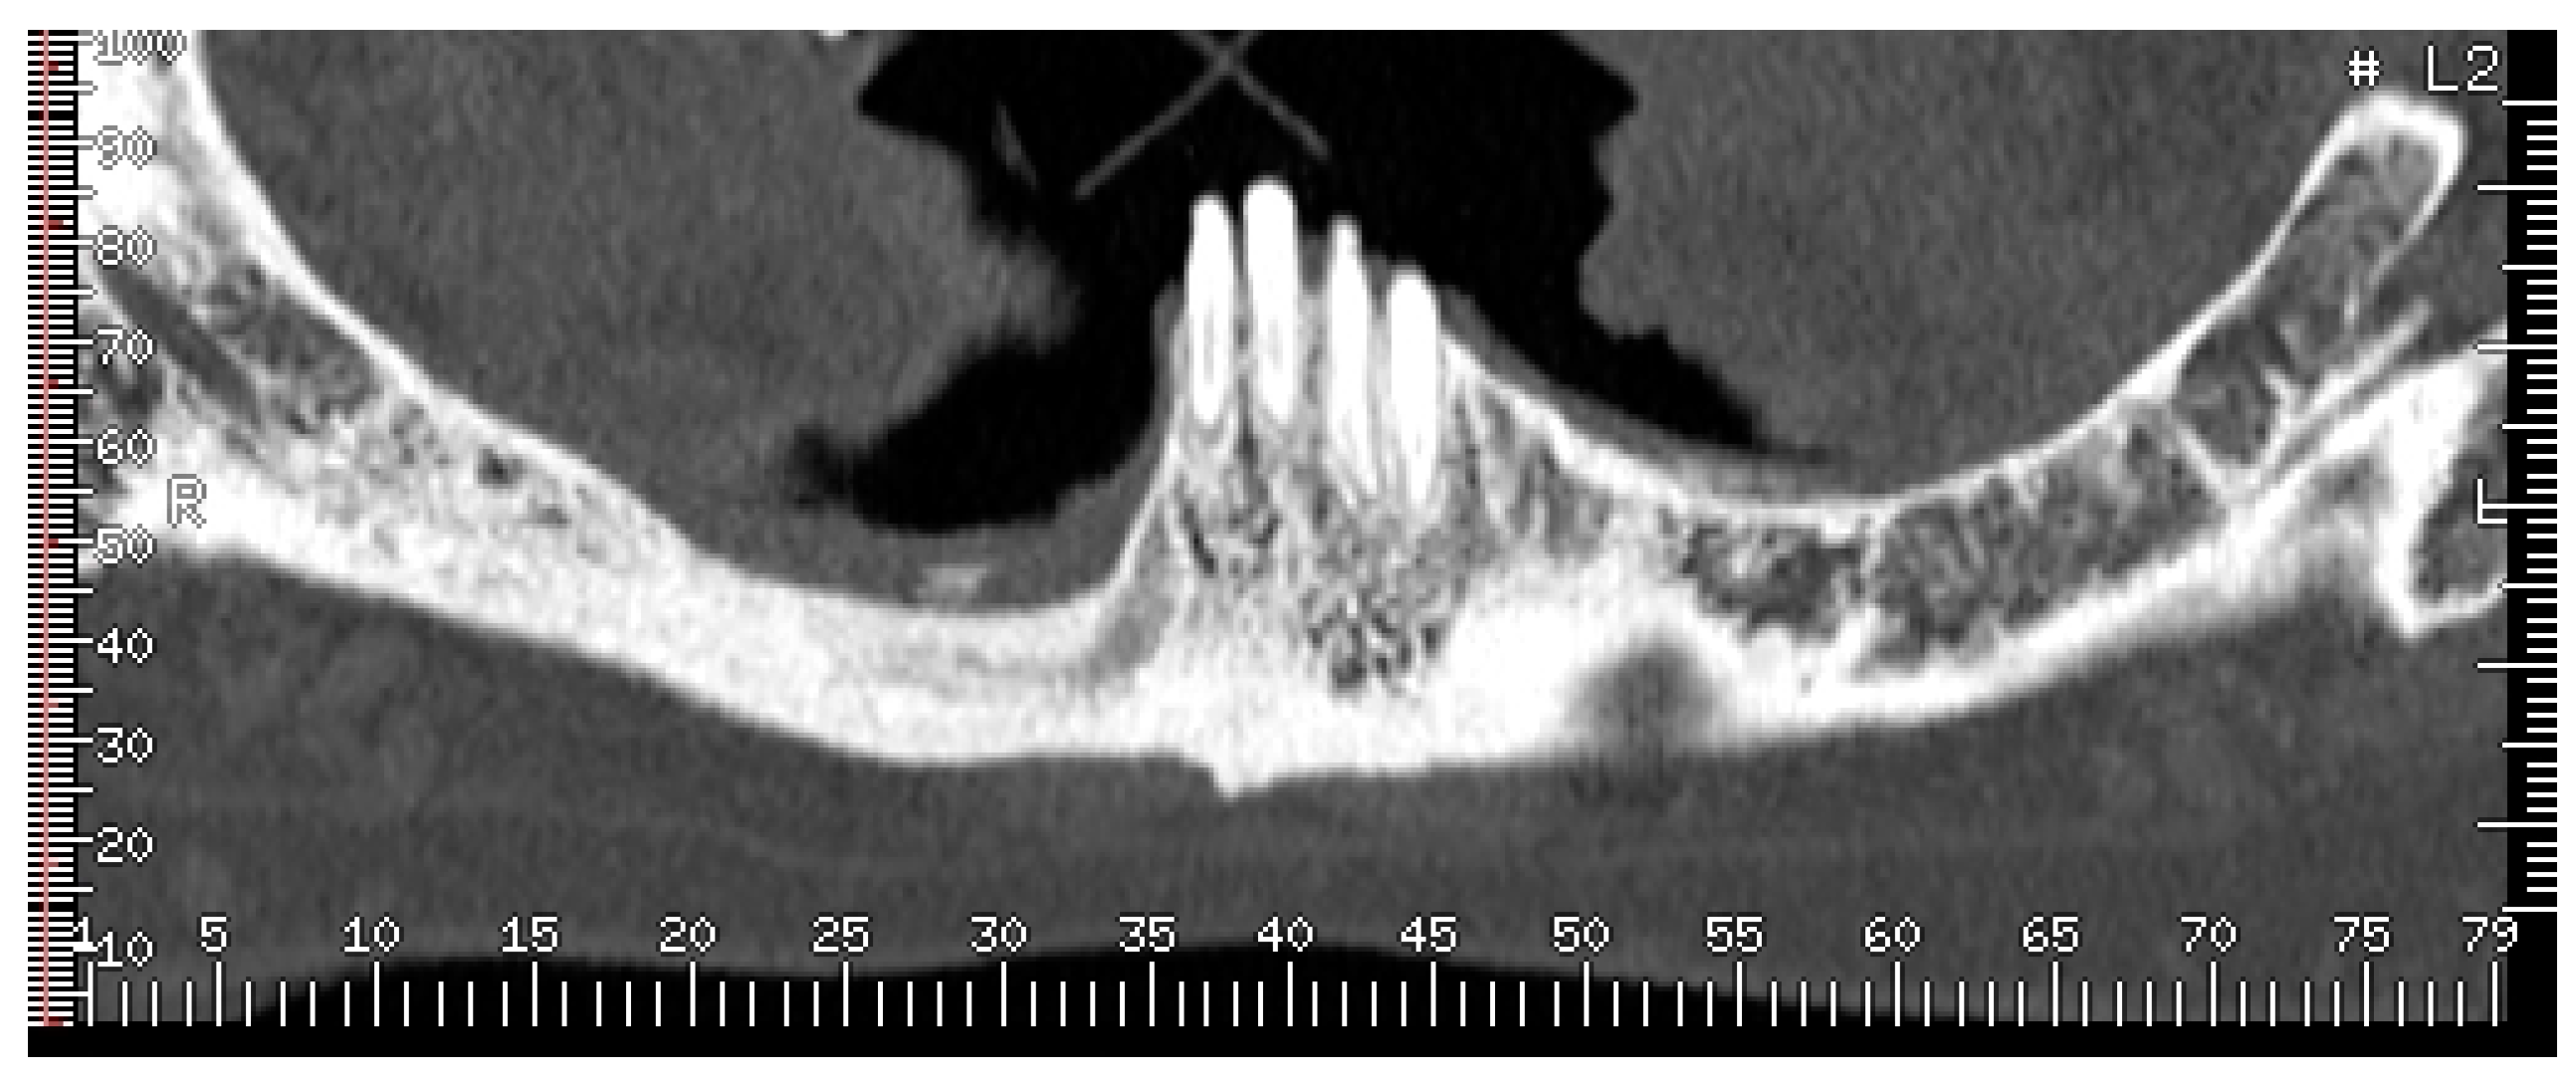

2. Case Report